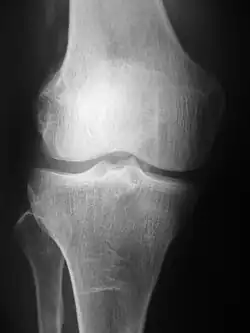

Projection (plain) radiography

Radiographs (originally called roentgenographs, named after the discoverer of X-rays, Wilhelm Conrad Röntgen) are produced by transmitting X-rays through a patient. The X-rays are projected through the body onto a detector; an image is formed based on which rays pass through (and are detected) versus those that are absorbed or scattered in the patient (and thus are not detected). Röntgen discovered X-rays on November 8, 1895,[5] and received the first Nobel Prize in Physics in 1901 for this discovery.[6] In film-screen radiography, an X-ray tube generates a beam of X-rays, which is aimed at the patient. The X-rays that pass through the patient are filtered through a device called a grid or X-ray filter, to reduce scatter, and strike an undeveloped film, which is held tightly to a screen of light-emitting phosphors in a light-tight cassette. The film is then developed chemically and an image appears on the film. Film-screen radiography is being replaced by phosphor plate radiography but more recently by digital radiography (DR) and the EOS imaging.[7] In the two latest systems, the X-rays strike sensors that converts the signals generated into digital information, which is transmitted and converted into an image displayed on a computer screen. In digital radiography the sensors shape a plate, but in the EOS system, which is a slot-scanning system, a linear sensor vertically scans the patient.

Plain radiography was one of the earliest imaging modalities used in clinical medicine and remained the most widely used for several decades. Due to its broad availability, speed, and relatively low cost, it continues to be a common first-line tool in radiologic evaluation. Despite advances in CT, MRI, and other imaging techniques, there are many conditions in which traditional radiographs remain helpful in diagnosis. These include arthritis, pneumonia, bone tumors, fractures, congenital skeletal anomalies, and certain types of kidney stones.